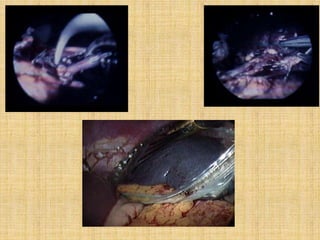

Laparoscopic Appendectomy

Control of mesoappendix

1. Endo GIA 2. Sutures

3. Endo loops 4. Surgical clips

5. Laser

6. Laparoscopic assisted

Laparoscopic Assisted

Appendectomy